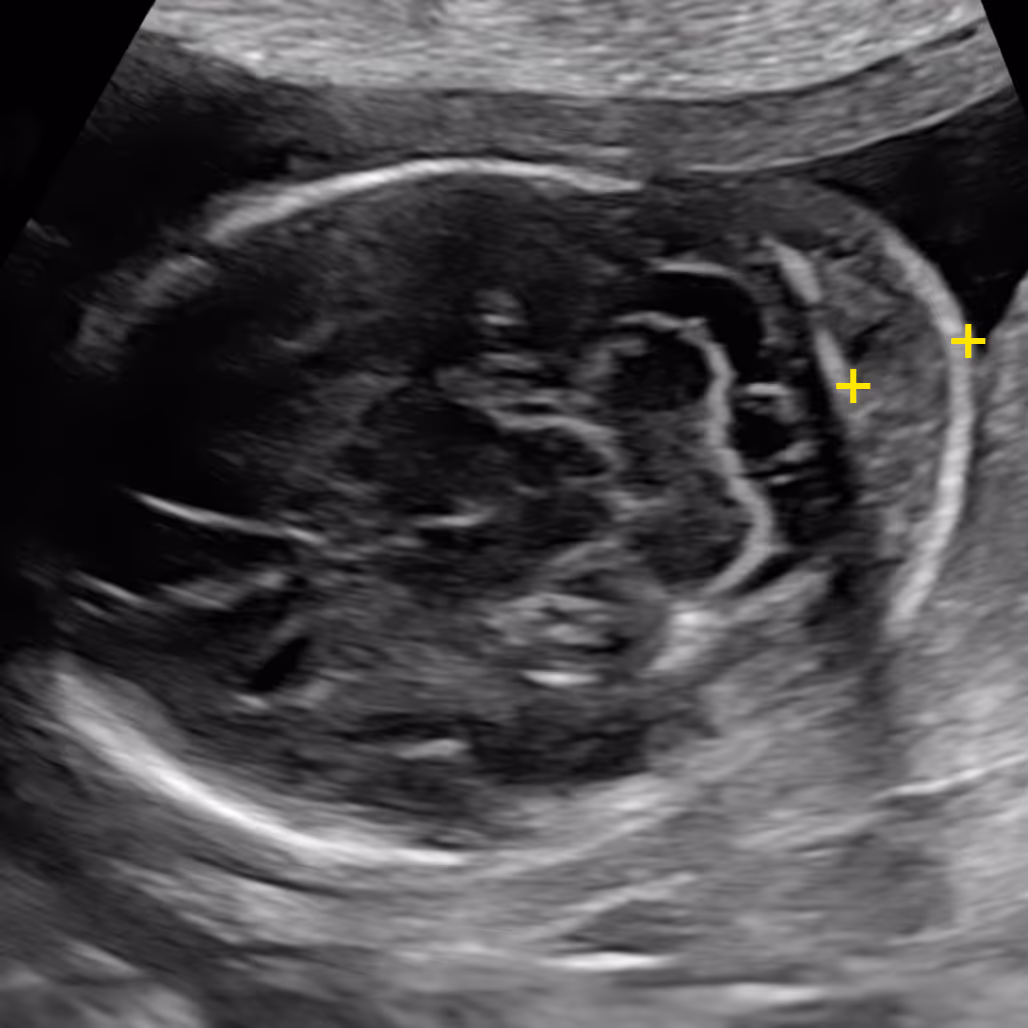

Yes. The measurement of NF is technically quite challenging and can change if the baby’s head and neck are extended or flexed, or if the baby is moving. This is why it should be done by an experienced sonographer or fetal medicine specialist, and sometimes repeated if the position is not ideal.

The nuchal fold (NF) is the thickness of the soft tissue (not fluid) at the back of the fetal neck. Increased NF is an ultrasound feature, not an anomaly. It was originally described by Prof Beryl Benacerraf in 1985 in the United States as the first soft marker for Down syndrome. The correct measurement of the nuchal fold in the second-trimester fetus is performed at the level of the posterior fossa, on a modified transverse view of the fetal head that includes the thalami, cerebellar hemispheres, and occipital bone. The NF is measured by placing the electronic callipers from the outer edge of the occipital bone to the outer skin surface.